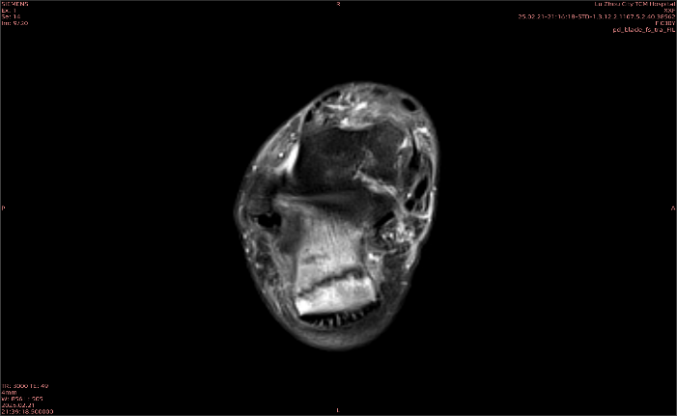

隱性骨折在MRI表現(xiàn)為T1WI序列上見由關(guān)節(jié)面向骨干走行的形態(tài)各異低信號區(qū),有線狀、條狀、紊亂低信號,信號強(qiáng)度不均勻。與T1WI低信號改變相對應(yīng)部位在T2WI上表現(xiàn)為相應(yīng)形狀的高、低混雜信號,且部分低信號周圍可見高信號水腫改變。STIR序列圖像上病灶呈顯著高信號,與信號被抑制的臨近正常骨髓形成鮮明對比,分界也較T2WI成像更為清楚。脂肪組織抑制技術(shù)是MRI的一個重要性能,脂肪抑制技術(shù)在MRI應(yīng)用中可以改善組織對比和增加病變顯示機(jī)會,這樣骨髓的脂肪抑制后就不會有任何信號,而隱性骨折線及骨髓水腫的異常高信號就會更加明顯的顯示出來。

舉例圖像

圖2

專業(yè)解釋看不懂沒關(guān)系,大家看圖1和圖2就可以了,這是同一個患者跟骨的磁共振和CT圖像,圖1的紅色箭頭指示的黑線就是磁共振圖像顯示的骨折線,一目了然。而對比圖2的CT圖像上并未顯示異常。

這下大家明白了吧,如果懷疑隱匿性骨折優(yōu)先選擇磁共振檢查